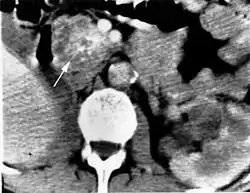

Nadnercza i pień współczulny

W nadnerczach lub pniu współczulnym pacjentów z zespołem von Hippla-Lindaua rozwija się guz chromochłonny nadnerczy (pheochromocytoma). Rzadsze są, dające podobne objawy, przyzwojaki (paraganglioma), rozwijające się z narządu Zuckerkandla. Guz chromochłonny w HLS rozwija się najczęściej w jednym albo obu nadnerczach, może też lokalizować się wzdłuż całego pnia współczulnego w obrębie jamy brzusznej, klatki piersiowej, szyi i głowy. W zespole Hippla-Lindaua pheochromocytoma rzadko złośliwieje. Objawy guza chromochłonnego to okresowe lub utrwalone nadciśnienie tętnicze, napady potów, bóle głowy, uczucie niepokoju, kołatanie serca, nudności, bóle brzucha, hipotensja ortostatyczna, hiperglikemia. Rzadko guz wydziela dopaminę mogącą dawać objaw hipotonii, albo ACTH, dając objawy hiperkortyzolemii. Około 5% pacjentów z HLS umiera w przełomie nadnerczowym[3].